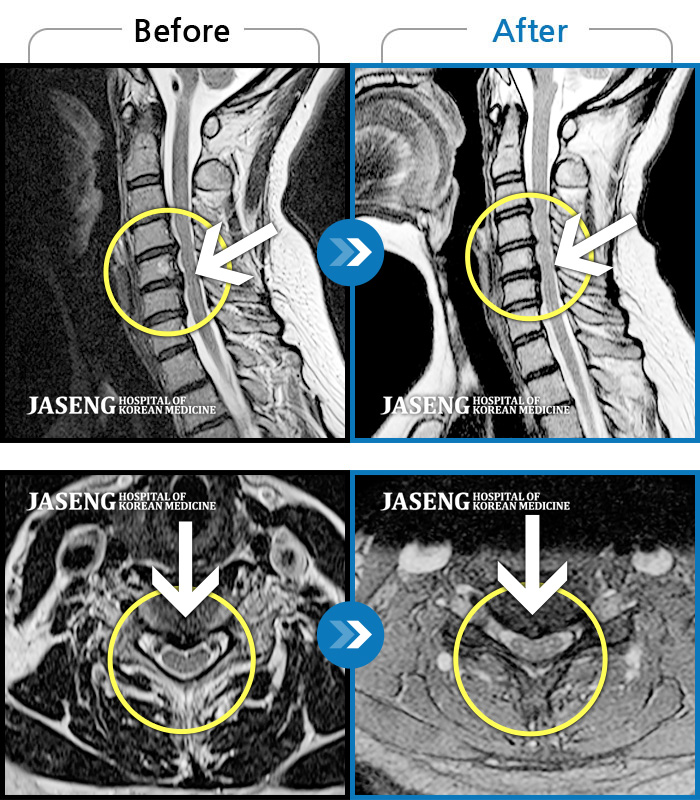

목디스크

인천 · 조남훈 원장

목도 아프고 양팔도 저리고, 어지러움도 있어요.

촬영시기

2019.08.28 ~ 2020.12.29

2021.01.08

조회수 141